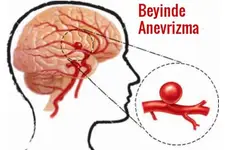

Bebeklerde beyin kistleri, genellikle doğumdan önce veya doğum sırasında oluşabilen sıvı dolu keseciklerdir. Bu kistler, beyin dokusunda veya çevresinde yer alabilir ve çoğu zaman zararsızdır. Ancak bazı durumlarda, beyin kistleri beyin fonksiyonlarını etkileyebilir ve tedavi gerektirebilir. Bu makalede, bebeklerde beyin kistlerinin belirtileri, tanısı ve tedavi yöntemleri hakkında detaylı bilgi verilecektir. Bebeklerde Beyinde Kist Belirtileri Bebeklerde beyin kistlerinin belirtileri genellikle kistin boyutuna, konumuna ve etkilerine bağlıdır. Belirtiler şunları içerebilir:

Tedavi süreci, her hasta için özeldir ve doktor tarafından titizlikle planlanmalıdır. Sonuç Bebeklerde beyin kistleri, çoğu zaman zararsız olsalar da, bazı durumlarda ciddi sağlık sorunlarına yol açabilir. Ebeveynlerin bebeklerinde herhangi bir belirti gözlemlediklerinde derhal tıbbi yardım almaları önerilmektedir. Erken tanı ve tedavi, bebeklerin sağlıklı gelişimi için kritik öneme sahiptir. Ekstra Bilgiler Bebeklerde beyin kistlerinin oluşumunda genetik faktörler, doğumsal anomali ve enfeksiyonlar etkili olabilir. Ebeveynlerin düzenli doktor kontrolü ile bebeklerinin sağlık durumunu takip etmeleri, olası sorunların önüne geçilmesine yardımcı olabilir. Ayrıca, bebeklerde beyin kistlerine dair farkındalığın artırılması, erken tanı ve tedavi süreçlerinin hızlanmasına katkıda bulunabilir. |

Hocam kusura bakmayin özür dilerim eşim 6 aylık hamile ve çocuğumuzun kafasında anekoik kistik lezyon görüldü tek birtane ve 18 16 mm çapın da ilerleyen zamanlarda bi sıkıntı olurmu

Merhaba, öncelikle eşinize ve size sağlık diliyorum. Bu tür kistik lezyonlar bazen bebeklerde görülebilir ve çoğu zaman kendiliğinden kaybolabilir. Ancak, doğru bilgi ve takip için mutlaka bir perinatoloji uzmanına veya kadın doğum uzmanına danışmanızda fayda var. Hepsinin ötesinde doktorunuzun önerilerini dikkate almanız en doğru adım olacaktır. Geçmiş olsun.